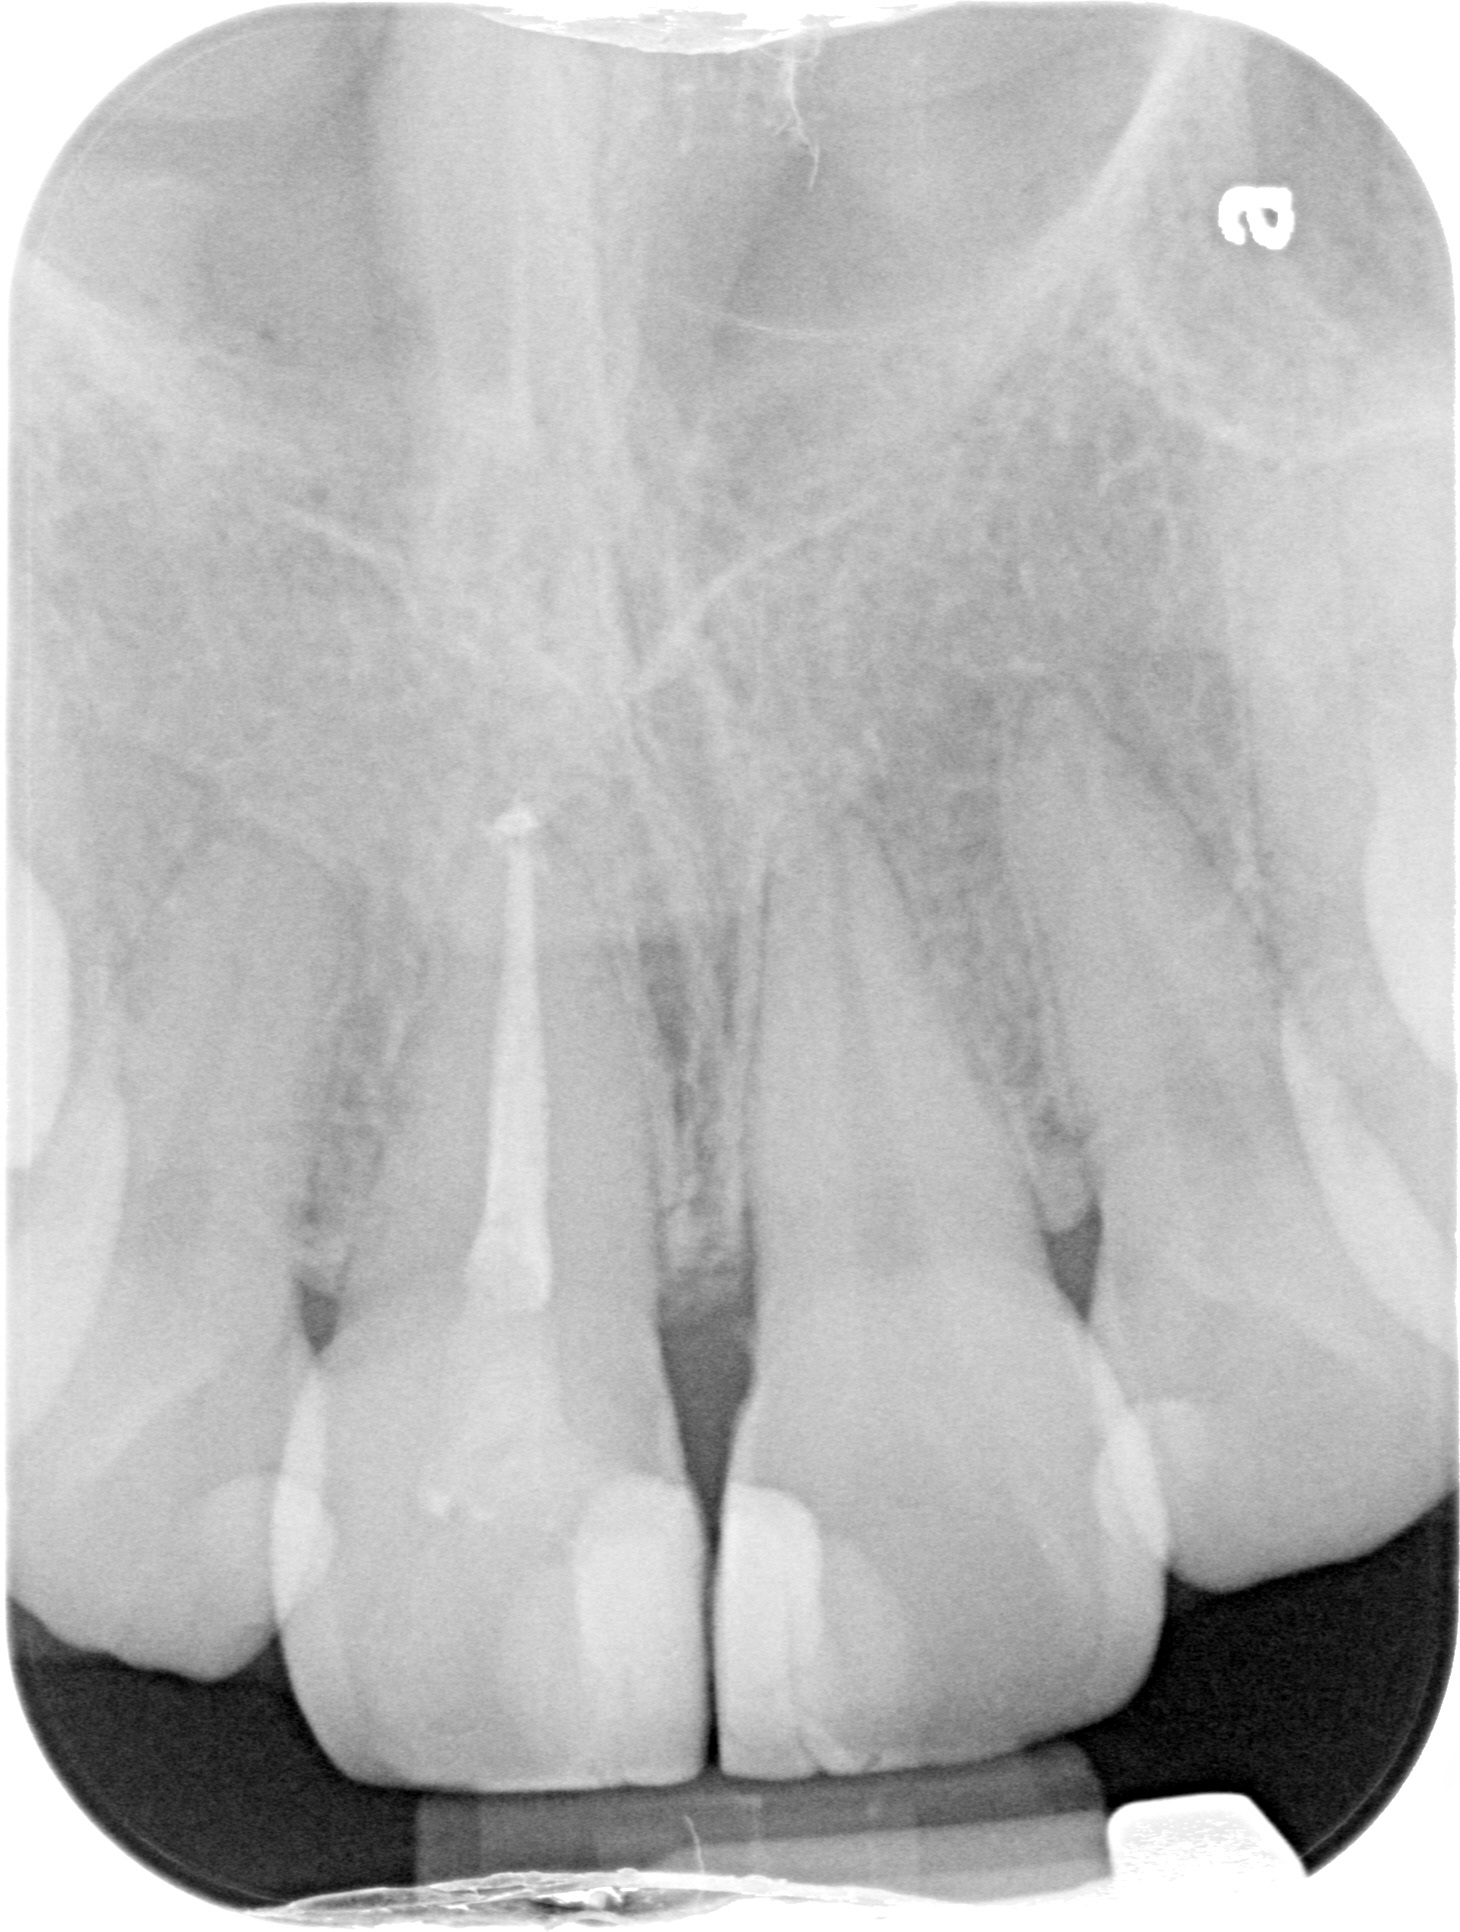

A CENTRAL INCISOR

INITIAL

WORKING LENGTH

FINAL

6 MONTHS FOLLOW-UP